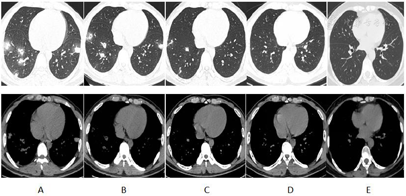

入院查体:T 38.0℃,P 111次/min,R 26次/min,BP 99/68 mmHg(1 mmHg=0.133 kPa),SpO2 90%(吸氧5 L/min),发育正常,神志清楚,对答切题,面色苍白,口唇轻度发绀;全身皮肤及黏膜未见明显瘀斑瘀点。呼吸急促,两肺呼吸运动对称,语音震颤未及增强及减弱。双肺呼吸音粗,未闻及干湿啰音;心脏及腹部查体无阳性体征。四肢肌力检查不配合,末梢发绀,双下肢无水肿。入院当天胸部CT:双肺多发空洞形成,考虑肺脓肿可能(图2A)。血常规提示:白细胞计数11.68×109/L,中性粒细胞占比0.875;C反应蛋白164.35 mg/L。降钙素原>158.51 ng/ml。血红蛋白111 g/L,血小板计数12×109/L。乳酸2.4 mmol/L。入院后立即留取浓痰液送常规生化、病原学等,多次抽取血培养送检,完善骨髓穿刺、铁染色、骨髓活检及流式细胞等检查,安排纤维支气管镜等检查。

经评估后经验性给予美罗培南联合万古霉素抗感染治疗,同时先后给予辐照单采血小板(2治疗量)、重组人血小板生成素(15 000 U、每日1次、3 d)补充血小板,辅以解痉、祛痰、增强免疫、抗炎、纠正电解质、补液、血管活性药物等对症治疗,进一步行呼吸道病毒抗原、流感病毒抗原、肺炎支原体培养、结核分枝杆菌、病毒性肝炎、MRSA、梅毒和人类免疫缺陷病毒筛查均为阴性;肝肾功能、电解质和凝血功能均无明显异常。SOFA评分为11分。APACHEⅡ评分10分。2 d后血培养提示星座链球菌(厌氧及需氧血培养瓶结果),药敏提示对青霉素、万古霉素、利奈唑胺、左氧氟沙星、喹努普汀等抗菌药物敏感,继续原方案治疗;1周后患者体温回归正常,症状明显缓解,复查胸部CT见双肺空洞较前有所减小,白细胞、C反应蛋白、降钙素原逐渐下降,血小板恢复正常,患者病情稳定,转入普通病房继续治疗并停用美罗培南,停用升血小板药物等药物;2周后患者病情明显好转,一般情况较好,再次复查CT见空洞较前明显减小,患者体温正常无明显波动,白细胞、C反应蛋白、降钙素原恢复正常。但血小板继续上涨,高达867×109/L,血小板功能正常,D2聚体升高,予以阿司匹林联合氯吡格雷抗血小板预防血栓形成。

出院后口服阿莫西林克拉维酸钾继续抗感染治疗。1个月后患者门诊复查,自诉无明显特殊不适,体温正常,双肺呼吸音清,复查胸部CT见双肺炎性病灶明显吸收,白细胞、C反应蛋白,降钙素原均正常,血小板恢复正常。2个月后患者症状完全缓解,体温正常,双肺呼吸音清,门诊复查胸部CT未见异常,白细胞、C反应蛋白、降钙素原均正常,血小板恢复正常。患者痊愈。